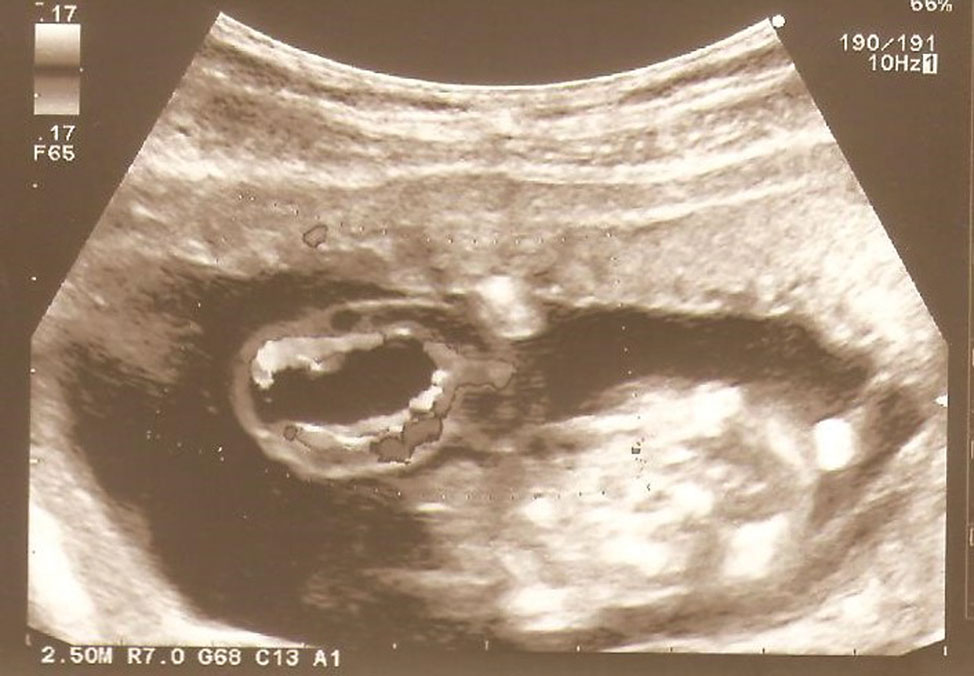

A 24-year-old primigravid patient was referred to the tertiary perinatal centre in the 14th week of gestation due to the ultrasound finding of an umbilical cord tumour. The results of the first trimester combined test done in the 13th week of gestation were of low risk. The current ultrasound examination revealed fetal biometry at the 14th week of gestation with visible body movements. The nuchal translucency measured 1.3 mm. The only ultrasound finding of the fetus was a small bilateral pyelectasis measuring 2 mm with normal renal parenchyma and urinary bladder. On the fetal side of the umbilical cord around 5 cm from the insertion ultrasound revealed an anechoic cystic mass measuring 4.8 mm in diameter located in the central part of the cord with the umbilical vessels located against the outer wall detected by colour Doppler ultrasonography (Figure 1). The rest of the umbilical cord and placentation were normal. The patient was offered an invasive prenatal diagnostic test which she refused.

Ultrasound examination at the 14th week of gestation revealing an anechoic cystic mass measuring 4.2 mm in diameter located in the central part of the cord with the umbilical vessels located against the outer wall detected by colour Doppler.

The typical ultrasound picture of the allantoic cyst includes the separation of the umbilical cord blood vessels divided with the well-distinguished anechogenic structure in the middle part of the cord without a positive blood flow within the cyst which was shown in our case (Figure 1) [6]. Doppler sonography can be very helpful in differential diagnosis of rare umbilical cord vascular tumours such as haemangioma or angiomyxoma from rudimentary structures like an allantoic cyst or umbilical cord knots and pseudo-knots. Modern ultrasound techniques such as B-mode ultrasonography and tree- and four-dimensional ultrasound have also been shown to be beneficial in diagnosis of umbilical cord cysts [7].